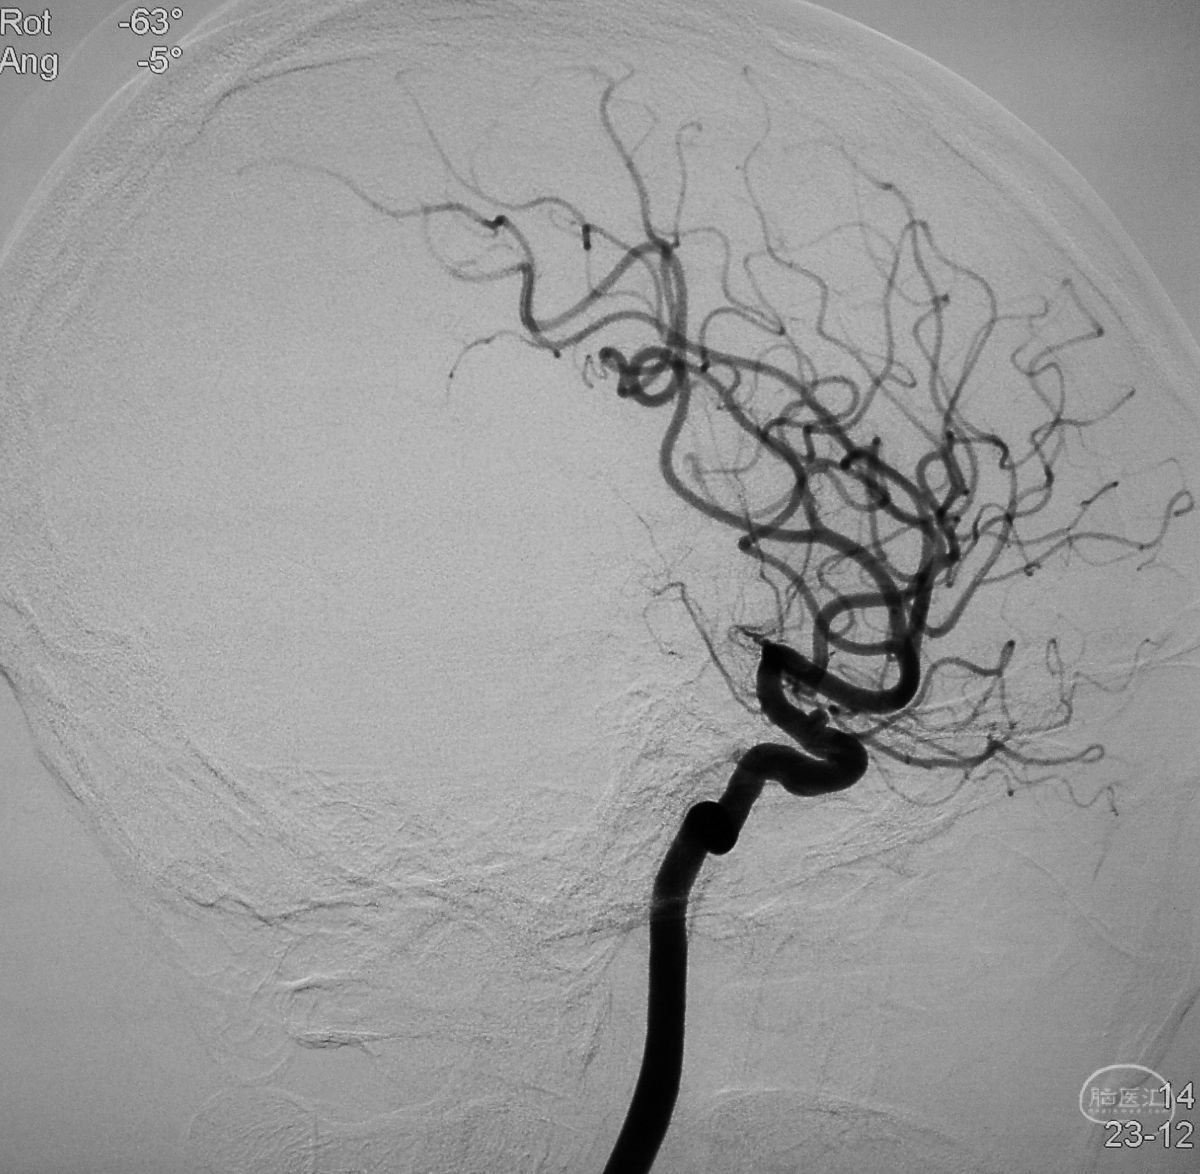

工作位造影

Traxcess 14微导丝可以进入瘤腔,但头端塑成S形的Echelon 10微导管无法跟入。

将微导管在虹吸弯处成襻,越过瘤颈,管头折返钩入瘤腔,即所谓回马枪技术。